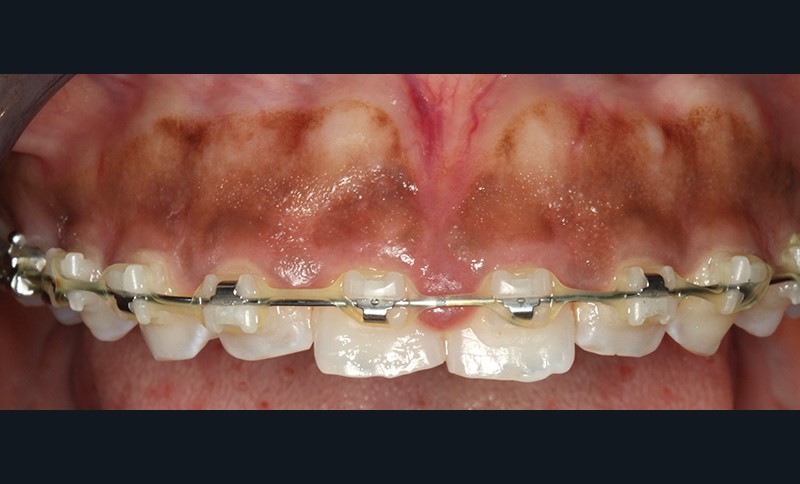

Une patiente de trente ans, traitée orthodontiquement pour une bi-proalvéolie (fig. 1) aggravée par la présence de diastèmes antérieurs et par une supraclusion incisive, consulte pour une hyperplasie gingivale supérieure disgracieuse dans le secteur 14-24 (fig. 2) alors qu’elle est en phase finale (J-60) du traitement orthodontique. L’hyperplasie est apparue au cours du traitement orthodontique dont le but consistait à réduire la projection incisive, à diminuer le sourire gingival par impaction incisivo-canine supérieure et à fermer les diastèmes.